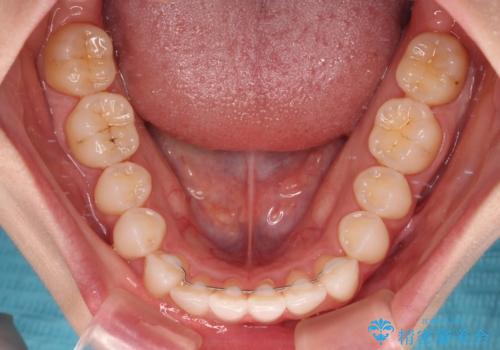

- 前歯のデコボコと下の前歯が隠れてしまう咬み合わせを気にして来院された患者様です。

インビザラインによる上下歯列の拡大と、IPR(歯と歯の間を削る)にるスペースの獲得により、口元のデコボコとディープバイトを改善することとしました。

インビザラインは、装着していない時間がどれだけ短いかが、治療期間を大きく左右します。こちらの患者様は1日22時間以上、毎日欠かさず装着してくださったため、1年弱という短期間で満足のいく歯列に整えることができました。